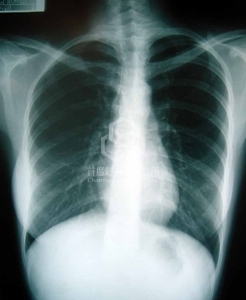

另一方面, 患者亦有如上一篇文章: 脊柱側彎(scoliosis)的問題.

脊柱側彎

隆乳手術必須注意調整義乳容積, 才能做到勻稱對稱的胸形. 最後兩邊義乳相差40cc.

脊柱側彎(scoliosis)是大部份醫師會忽略的問題, 也是書本沒有教的知識, 所以通常會導致整形醫師做出不佳的判斷. 上述消費者脊柱側彎27度, 先天上左邊就比較大, 醫師忽略的話, 造成術後仍舊不對稱, 乳下線高低差.

更慘的是產後一哺乳, 萎縮下去義乳原形畢露, 除了一大一小, 乳房更變硬. 所以脊柱側彎的問題絕對不能等閒視之. 詳細文章請參考站長的文章: 乳房不對稱(產後萎縮與胸闊異常)